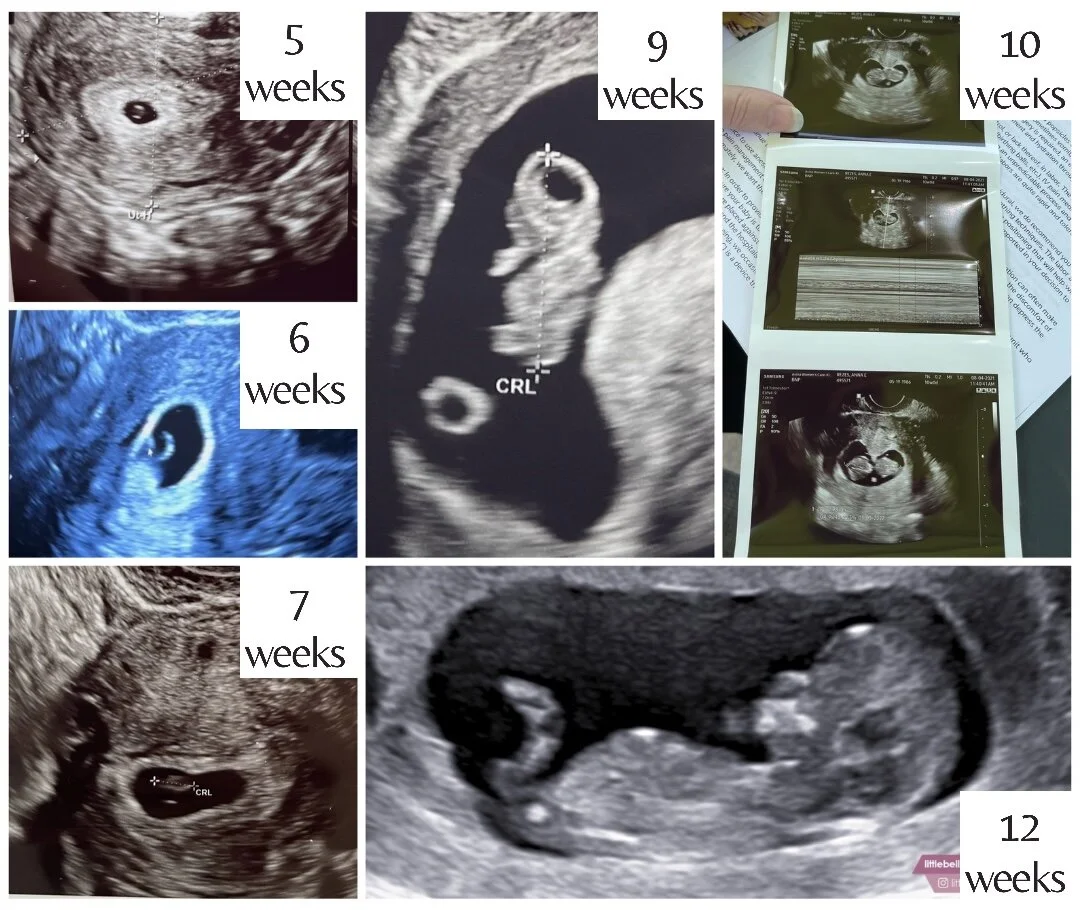

After the first positive pregnancy test, I rechecked test after test, analyzing the progression lines of each one. Then came the blood draws. My first number was good, and two days later, my numbers doubled, which indicates a true pregnancy. Then my reproductive doctor was scheduling my first ultrasound to ensure the baby was where it should be. I was five weeks one day pregnant for my initial ultrasound. The pregnancy clock starts on the first day of your last period, which means the day they transferred the embryo into my uterus, they already considered me two-and-a-half weeks pregnant. Weird, right? But most people don’t know precisely when they conceive.

At week nine, I had my fourth ultrasound, and we graduated from our fertility clinic. Week ten, I had the first ultrasound with my OB. Our little baby kept measuring a few days behind, but her heartbeat has always been strong, and by week twelve, she was measuring ahead of schedule. She even did a little dance for us as we watched her on the ultrasound screen.

All the ultrasounds so far